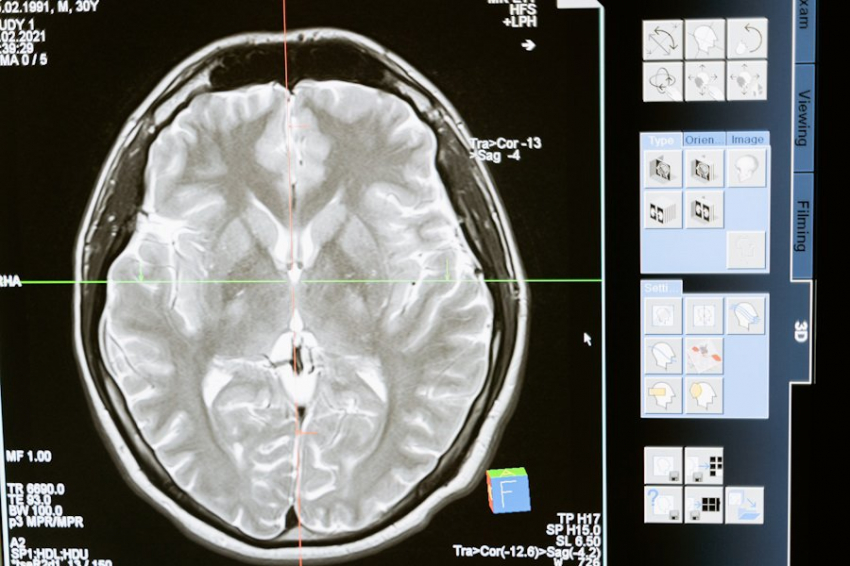

Мозгу приходится быстро удалять лишние «файлы» из рабочей памяти, дабы освободить место под новую информацию. Фрагменты либо переходят в долгосрочную память, либо уходят из области сознательных мыслей. Многозадачность — непростая задача для мозга. Научиться ей поможет развитие префронтальной коры головного мозга, являющейся зоной сложного обучения, принятия решений и логики.